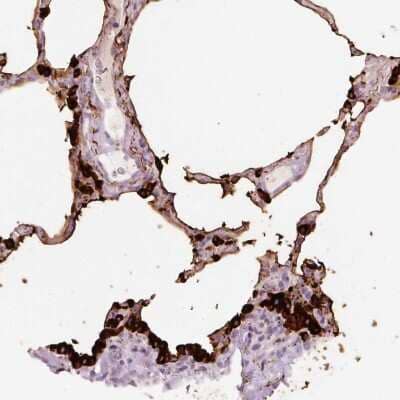

Immunohistochemistry-Paraffin: STEAP1 Antibody [NBP2-48603] - Staining of human lung shows strong cytoplasmic and membranous positivity in pneumocytes.